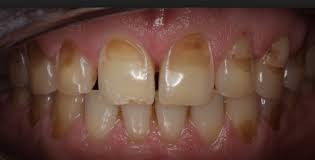

Because enamel is translucent, you can see light through it. But the main portion of the tooth, the dentin, is the part that's responsible for your tooth color -- whether white, off white, grey, or yellowish.

Discoloration. As the enamel erodes and more dentin is exposed, the teeth may appear yellow.

Cracks and chips. The edges of teeth become more rough, irregular, and jagged as enamel erodes.